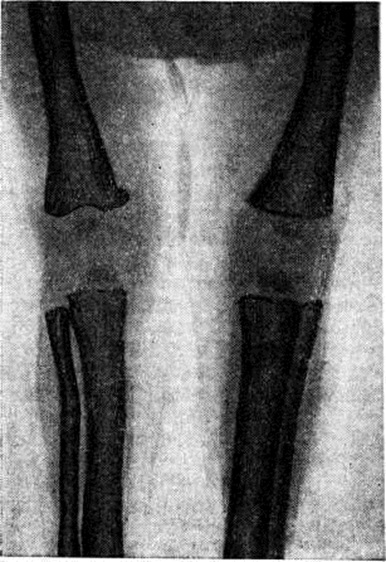

Рентгенологически — выраженные симметричные периостальные наслоения, утолщение компактного и склероз губчатого вещества диафизов длинных и коротких трубчатых костей верхних и нижних конечностей (рисунок), а также ключицы и нижней челюсти. Эпи- и Метафизарные отделы костей остаются не поражёнными. Периостальные наслоения часто резко ограничены и иногда имеют пластинчатый вид. Отмечаются дугообразные искривления большеберцовой кости.

Рис

Рентгенограмма нижних конечностей ребёнка 4 месяцев, страдающего гиперостозом. Выражены симметричные периостальные наслоения, склероз губчатого вещества.